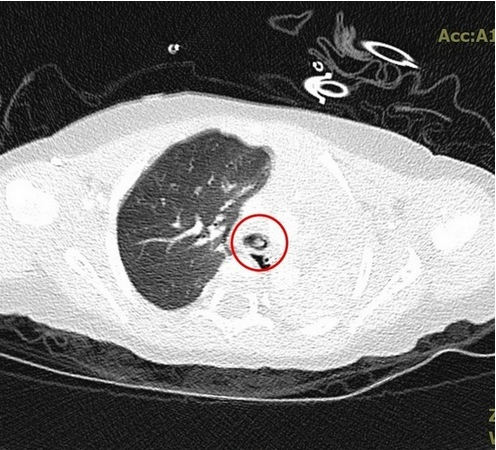

不滿一歲的小佩(化名)抵達花蓮慈院急診室時,已有明顯膚色變暗、意識不清且身體些微抽搐等缺氧症狀,為避免孩子持續缺氧造成身體損傷,當時在急診值班的兒科病房主任陳明群很快地幫她放入氣管內管,讓肺部能夠獲得足夠的氧氣,並立刻安排進行X光檢查,發現小佩的左邊肺部已經呈現白色塌陷狀態,而右肺部則有過度充氣的現象,團隊進一步做電腦斷層排查原因,找到了原因就是卡在左支氣管入口的異物。小佩很快的從急診轉往兒童加護病房,在初步解決危急情況後,醫療團隊於當日上午利用支氣管鏡檢查,將異物取出,發現這個奪走孩子呼吸的東西,是長3.5公分、寬0.5公分的硬式隱形眼鏡吸棒,所幸把吸棒拿出來後,小佩的恢復情況良好,在二十一日順利出院返家。

左圖:醫療團隊透過支氣管鏡檢查,看到異物塞在左支氣管開口處。

中圖:團隊進一步做電腦斷層排查原因,發現是卡在左支氣管入口的異物使氧氣無法進入左肺部。